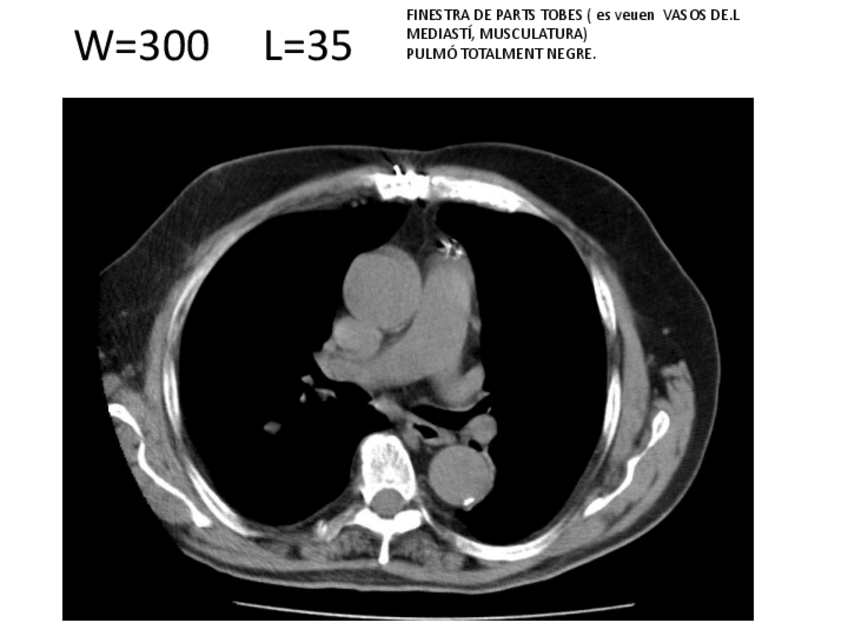

generalidades

He publicado nuevos apuntes de Técnicas de Tomografía Computarizada y Ecografía: generalidades

EXEMPLESDEFINESTRES.pdf